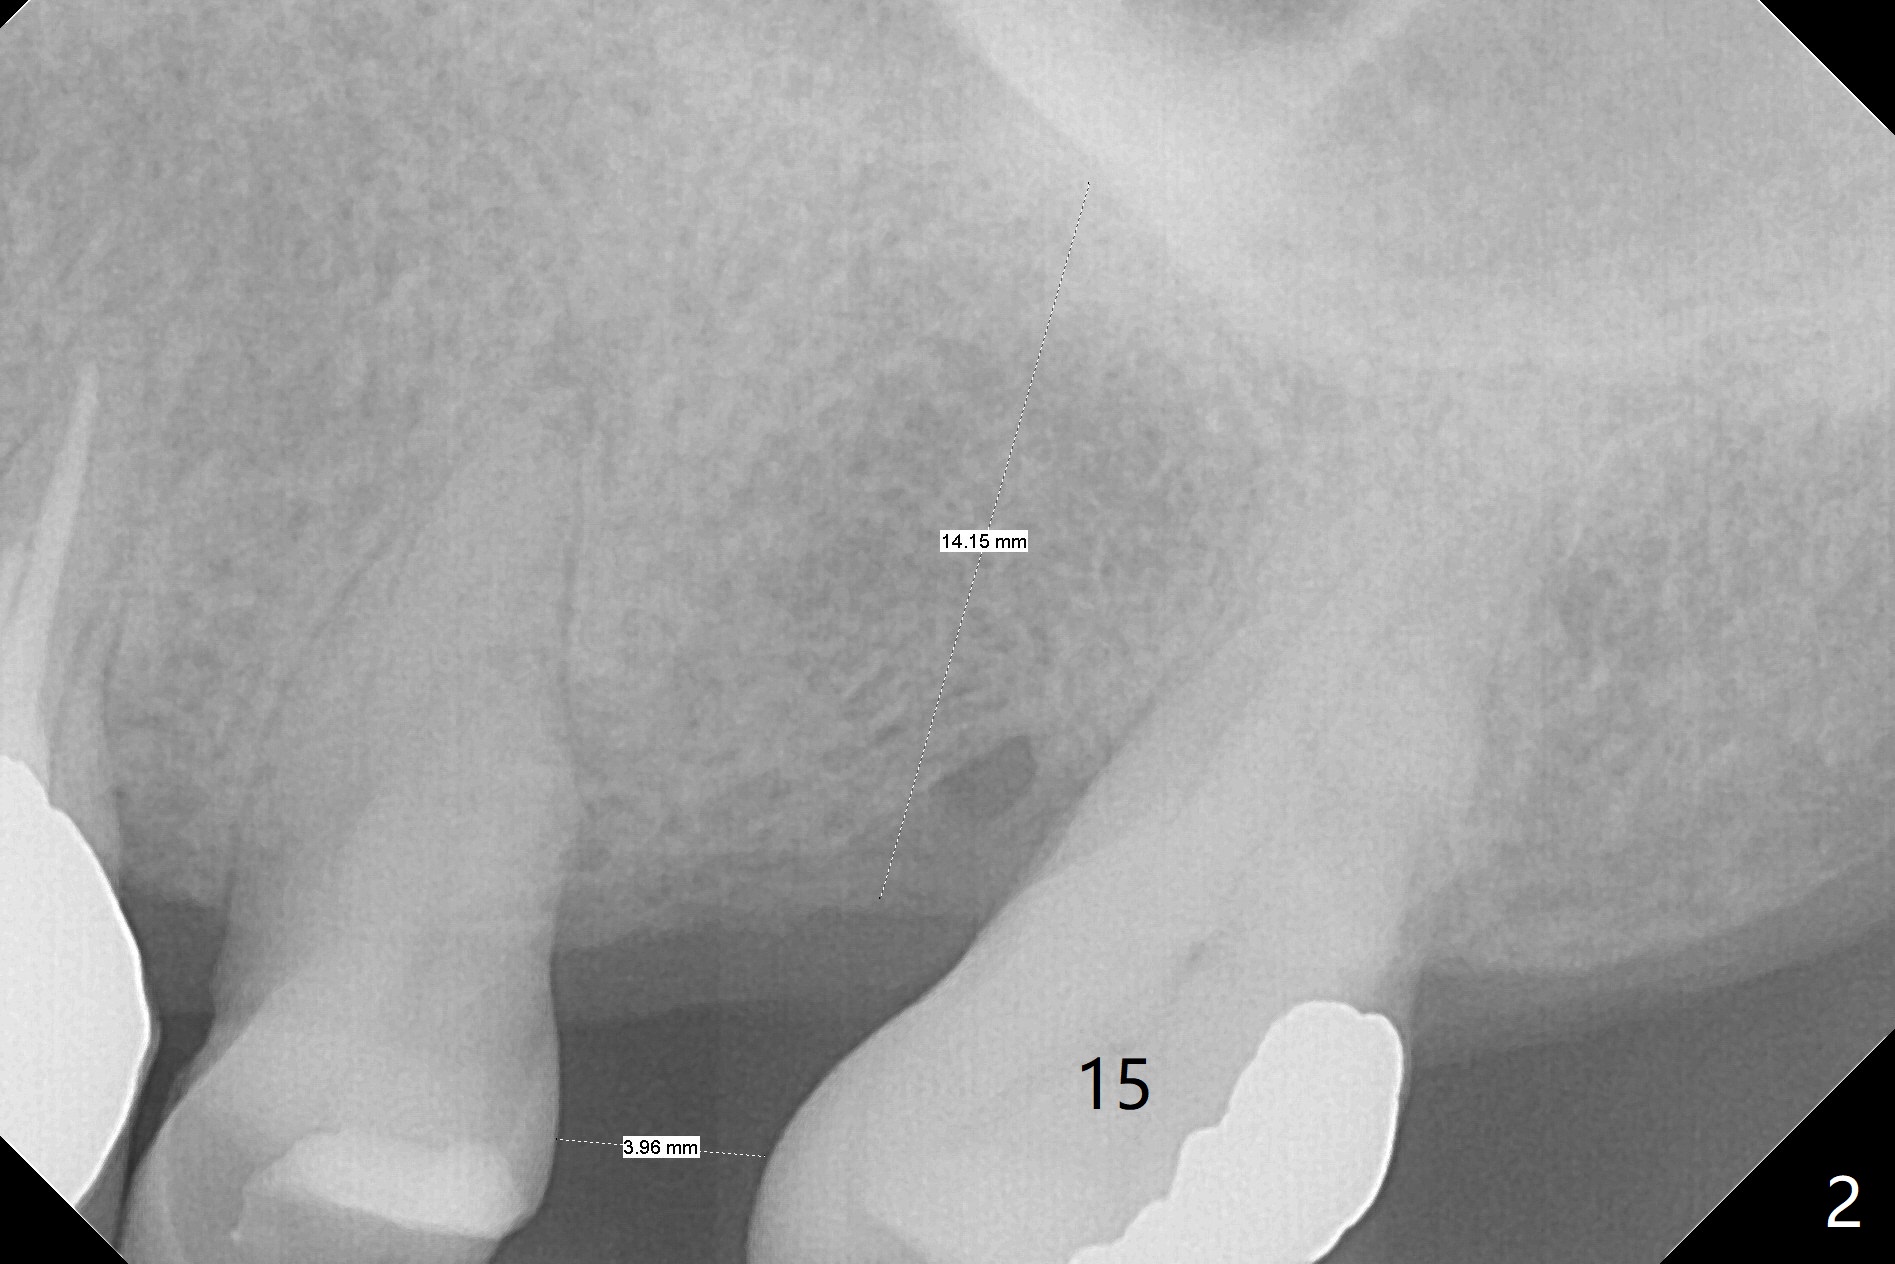

A 64-year-old man has multiple restorations. The tooth #2 seems to have root resorption. The tooth #27 has recently finished RCT. It appears necessary to establish sound occlusion on the left side by placing an implant at #14. First at all, the mesially tilted tooth #15 needs to be uprighted (Fig.2). The implant crown at #10 will be used as an anterior anchorage, since the three teeth (#11-13) are usually not strong enough to distalize the 2nd molar. To prevent debracketing at #10, a diamond bur will be used to roughen the crown surface and new bonding agent is applied. The second easily debracketing spot is #12 (crown), which could be used bicuspid band. The 3rd option to reduce debracketing is not to use rectangular wire initially. When the space at #14 increases to 8 mm mesiodistally, an implant will be placed. Once the implant is osteointegrated, a band is applied. From that point on, a rectangular wire could be used. If debracketing occurs at #10, it does not matter, as the posterior anchorage has taken over. Save all of wires used initially, since wires may have to return to thinner ones when #14 band is loaded. To unlock the occlusion (to distalize #15 without interference), composite will be applied to one of FPDs on the right side. The distal marginal ridge of the tooth #18 (Fig.1 *) may need to be trimmed.